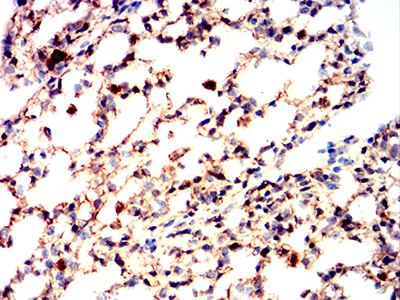

Immunohistochemical analysis of paraffin-embedded Mouse lung using BAX mouse mAb with DAB staining.